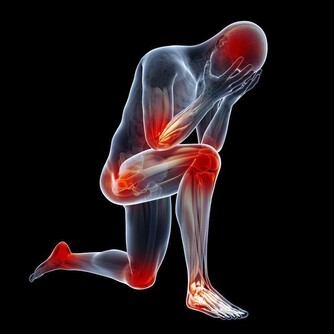

❶ 、【功能主治】養陰清肺,化痰益氣。用於肺熱燥咳、陰虛勞嗽、乾咳痰粘、氣陰不足、煩熱口乾。

❶、【性味】甘苦淡,涼。 ❷、【歸經】 入肺、脾經。 ❸、【功能主治】 養陰清肺,益胃生津。用於肺熱燥咳、勞嗽痰血、熱病津傷口渴。 10石斛

❶、【功能主治】養陰潤肺,清心安神。用於陰虛久咳,痰中帶血,虛煩驚悸,失眠多夢,精神恍惚。具有養陰潤肺止咳功效,用於肺陰虛的燥熱咳嗽,痰中帶血,如百花膏。治肺虛久咳,勞嗽咯血,如百合固金湯。具有清心安神功效,用於熱病餘熱未清,虛煩驚悸,失眠多夢等。藥用時煎服,10~30g。清心宜生用,潤肺蜜炙用。 ❷、【功效】養陰清熱,滋補精血。 16玉米須 玉米須味甘、淡,性平;歸腎、肝、膽經;質輕滲降;具有利尿消腫,平肝利膽的功效;主治水腫,小便淋瀝,黃疸,膽囊炎,膽結石,高血壓病,糖尿病,乳汁不通。有利尿降壓功能。 廣告 - 請繼續往下閱讀 17紅豆 ❶、【性能】味甘,性平。能健脾利濕,散血,解毒。 ❷、【用途】用於水腫、腳氣;產後缺乳,腹瀉、黃疸或小便不利;痔瘡,腸癰。 18杏仁

富含蛋白質、脂肪、糖類、胡蘿蔔素、B族維生素、維生素C、維生素P以及鈣、磷、鐵等營養成分。其性苦微溫,有小毒,滋潤養肺通便。適用於陰虛肺熱、咳嗽、咽乾舌燥、大便乾結者。 19羅漢果